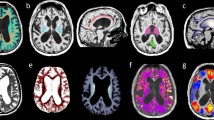

Color-coded T1 maps are only used for improved visualization and qualitative analysis (see representative cases in Fig. 2 of a typical iNPH T1 map and a T1 map of a patient in whom the diagnosis of iNPH was unlikely). Data analysis and ROI definition were performed using Fiji, an open-source image processing package based on ImageJ [35].

Representative axial T1 maps of a patient fulfilling all clinical criteria for iNPH and with improvement after CSF tap test (CSF-TT; left column a, c and e) and a case with an ambiguous clinical presentation without clinical improvement after CSF-TT (right colums b, d and f). Note the higher periventricular T1 relaxation times of the patient with high likelihood of iNPH diagnosis (left column as well as high T1 relaxation times at the anterior and posterior horn of the lateral ventricle (black arrows in c, e) compared to lower periventricular T1 relaxation times in the patient with unlikely iNPH diagnosis (right column) and no increases in T1 relaxation time at the anterior and posterior horn of the lateral ventricle (black arrows in d, f)

Representative cases demonstrating the ROI selection and qualitative differences in color-coded T1 maps are shown in Figs. 1 and 2. On baseline scans, T1 relaxation times in all ROIs were higher in iNPH patients compared to controls with highest differences found in the inferior anterior horn (1006.1 ± 93.1 ms vs. 911.4 ± 77.4 ms; p = 0.023, ∆T1 = 94.7 ms) and the superior posterior horn (982.9 ± 103.1 ms vs. 892.5 ± 68 ms; p = 0.037, ∆T1 = 90.4 ms) of the lateral ventricles (see Table 2 and Fig. 3).

Deep white matter hyperintensities were present to a comparable extent (Fazekas scale) in iNPH patients and controls in our study. Most interestingly, we found significant differences in T1 relaxation times at the superior anterior and inferior posterior horns of the lateral ventricle. In these regions CSF translocation is most frequently seen in iNPH patients. Therefore, T1 mapping represents an imaging technique not only visualizing subtle changes in this region, but also quantifying these changes. T1 relaxation times, however, seem to increase both with higher concentrations of CSF in the white matter (higher water content caused by CSF ependymal translocation) as well as with demyelination and axon loss (caused by small vessel disease), which both have been demonstrated in other studies [19, 22, 41, 42]. Therefore, T1 mapping might help to enrich the diagnostic work-up of iNPH to better distinguish imaging and clinical characteristics from patients with predominant small vessel disease, which normally do not improve after CSF-TT. In this respect, however, more scans in iNPH and age-matched controls are necessary to define cut-off values for periventricular T1 relaxation times that discriminate iNPH from other diseases like small vessel encephalopathy or AD.